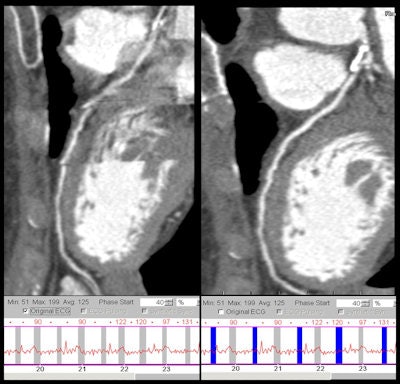

Patient weight is related directly to the scan quality, and the heavier the patient, the greater is the likelihood that the scan will be of poorer quality, Stirrup noted. Diagnostic accuracy is reduced in obese patients because the scan beam is significantly more attenuated as a result of increased tissue between the tube and the detectors; this is especially important when looking at small vessels. Image quality in patients who have a lot of calcium also may be reduced, particularly if narrowing of the vessels is under investigation. He advocates using beta-blockade to improve image quality for all patients regardless of CT scanner technology. Scanning those who have poorly controlled atrial fibrillation often results in a poor-quality image and such patients are often better served by an alternative imaging technique.

Heart rate control and fast gantry rotation time are important to perform single heartbeat acquisition scans, and the extent to which patients require beta-blockade/rate control depends on the scanner. Likewise, the choices for different rate control options can vary; e.g., glyceryl trinitrate (GTN) is popular in the U.S. for imaging distal coronary arteries because it is a potent vasodilator and improves opacity. Indications for use would be those patients who may have a predisposition to small vessel disease, such as smokers and diabetics. Stirrup recommends using a pro forma to document all procedural aspects, including heart rate control and any breath-holding sequences (and their effects) that need to be used during imaging.

"It is also important to get a good amplitude R wave when looking at optimizing images with correlated ECG, despite the fact that ECG leads need to be kept out of the area of interest," said Stirrup, who recommends placing pads on each shoulder and on the abdomen.